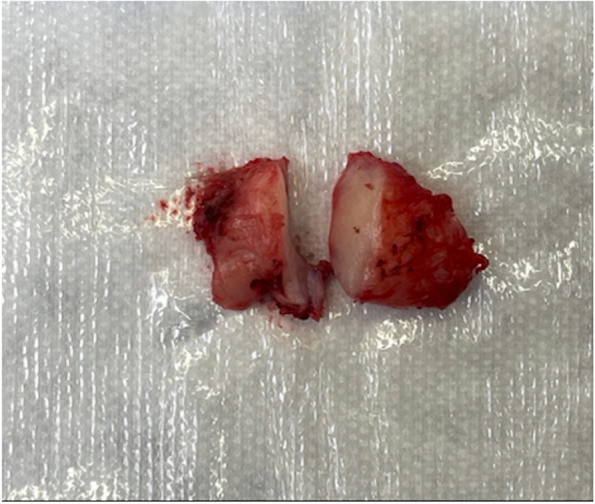

Symptoms did not improve with the oral antibiotics and steroids. Lacrimal gland biopsy was recommended. The patient underwent a left anterior orbitotomy with biopsy and removal of the mass, capsule intact. A 1.7 × 0.8 × 0.7 cm, grossly rubbery and fibrosed specimen (Fig. 3) was sent for fresh and formalin histopathological evaluation as well as flow cytometry and immunohistochemistry.

Fig. 3.

1.7 × 0.8 × 0.7 cm, grossly rubbery and fibrosed lacrimal gland specimen